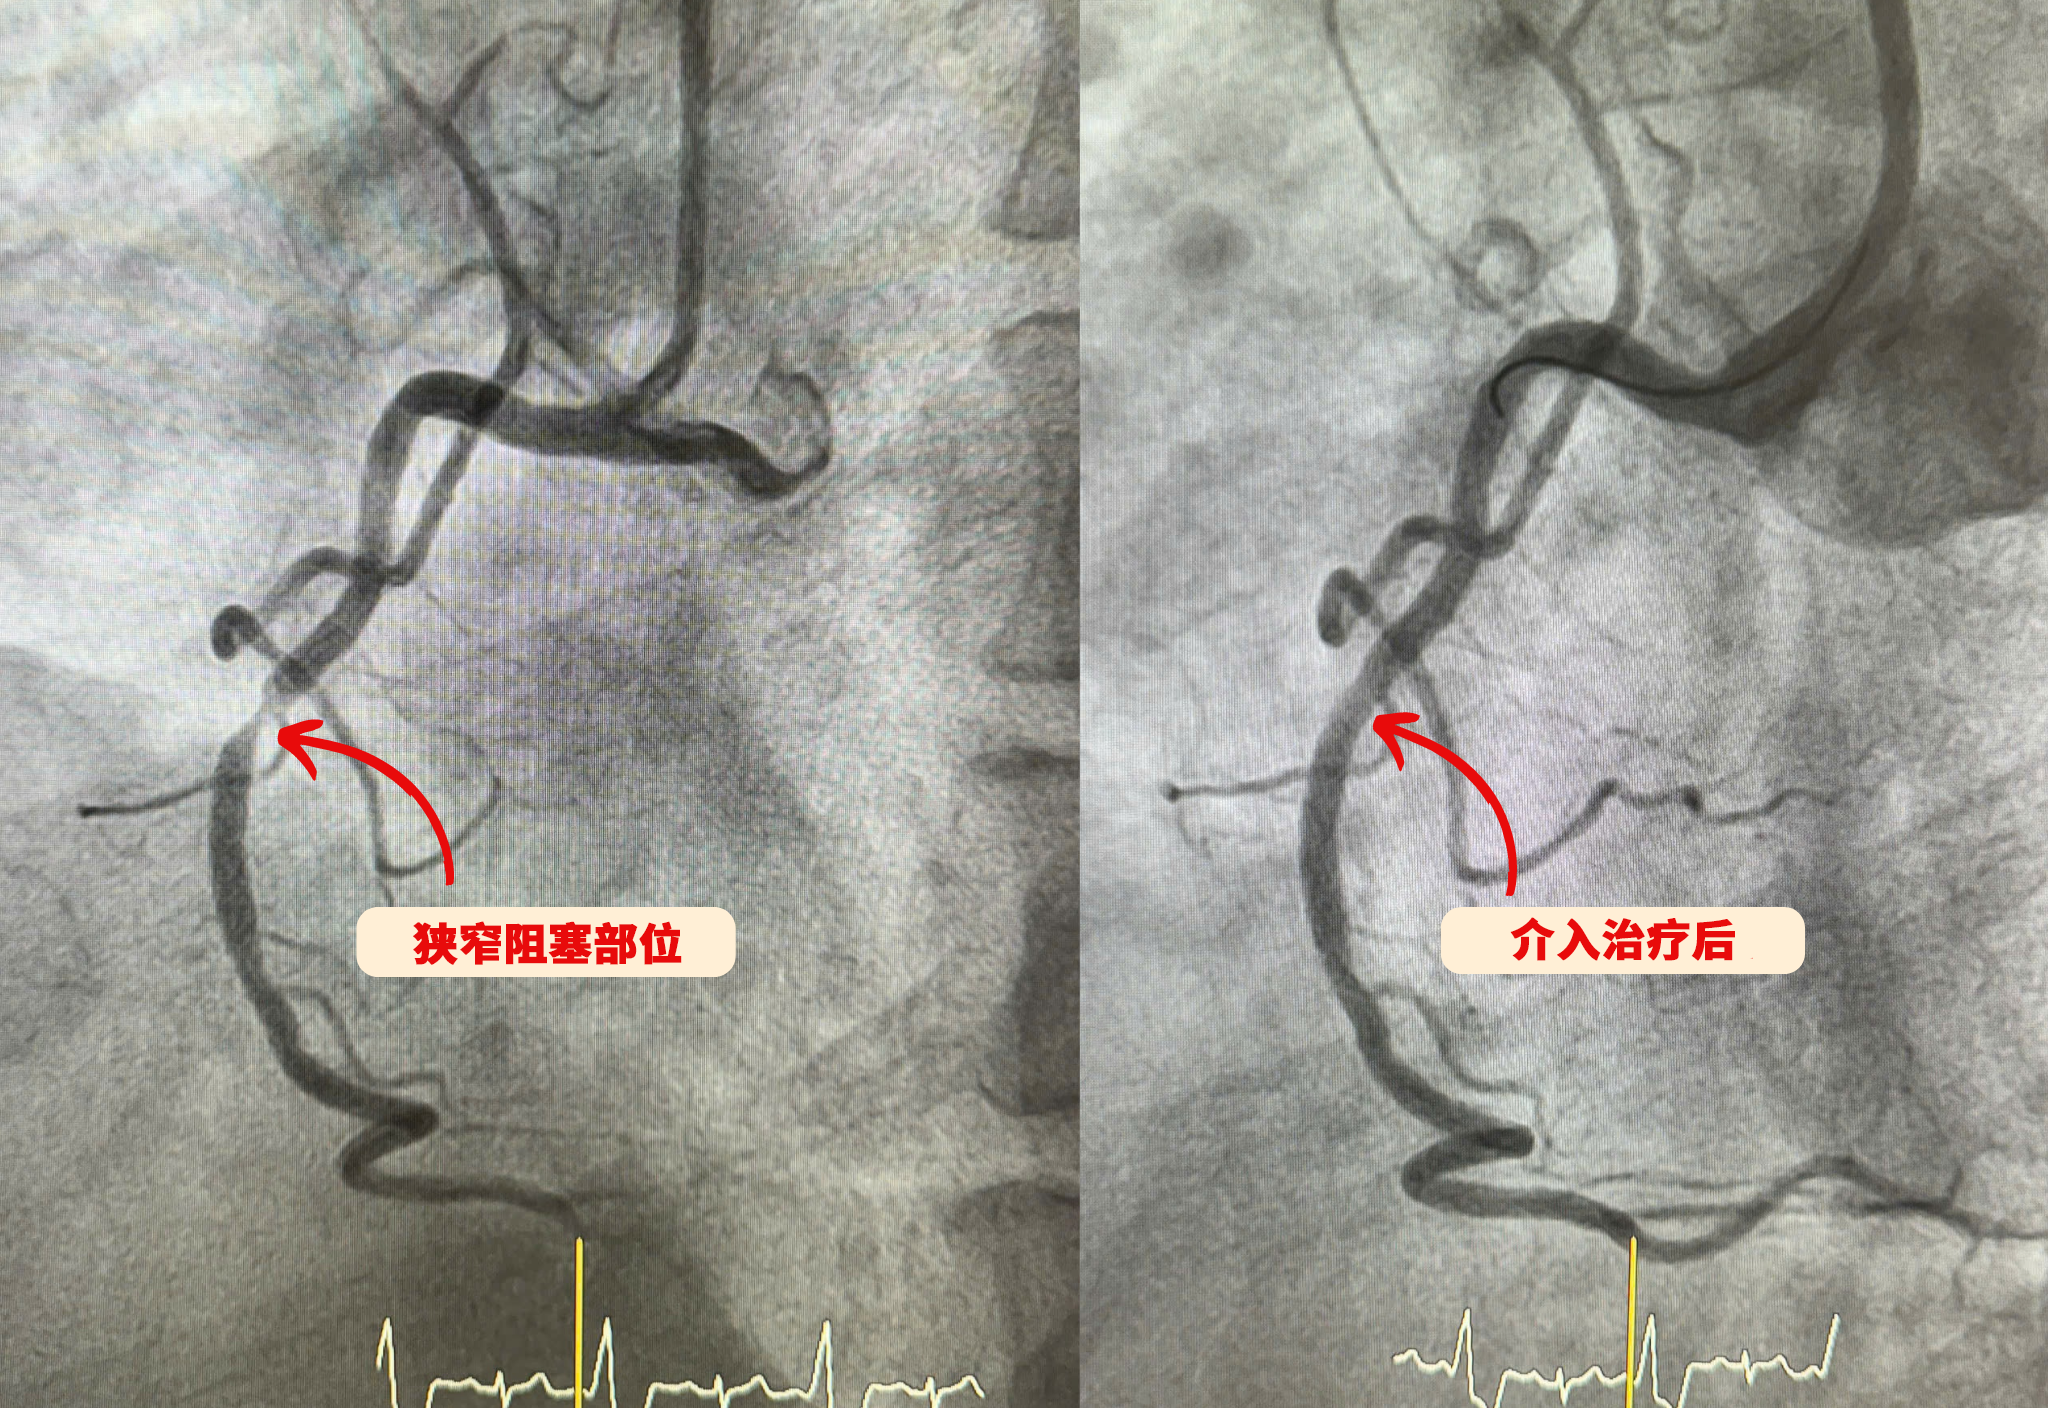

红玉综合医院成功应用药物涂层球囊技术治疗重度冠状动脉狭窄患者的干预前后情况

在红玉综合医院,药物涂层球囊扩张技术已成为常规开展的心血管介入手段,并成功应用于多种复杂病例,包括小血管病变、多发病变、支架内再狭窄等,同时确保高龄患者及合并多种基础疾病患者的治疗安全性。介入治疗后,患者恢复迅速,主要得益于以下优势: